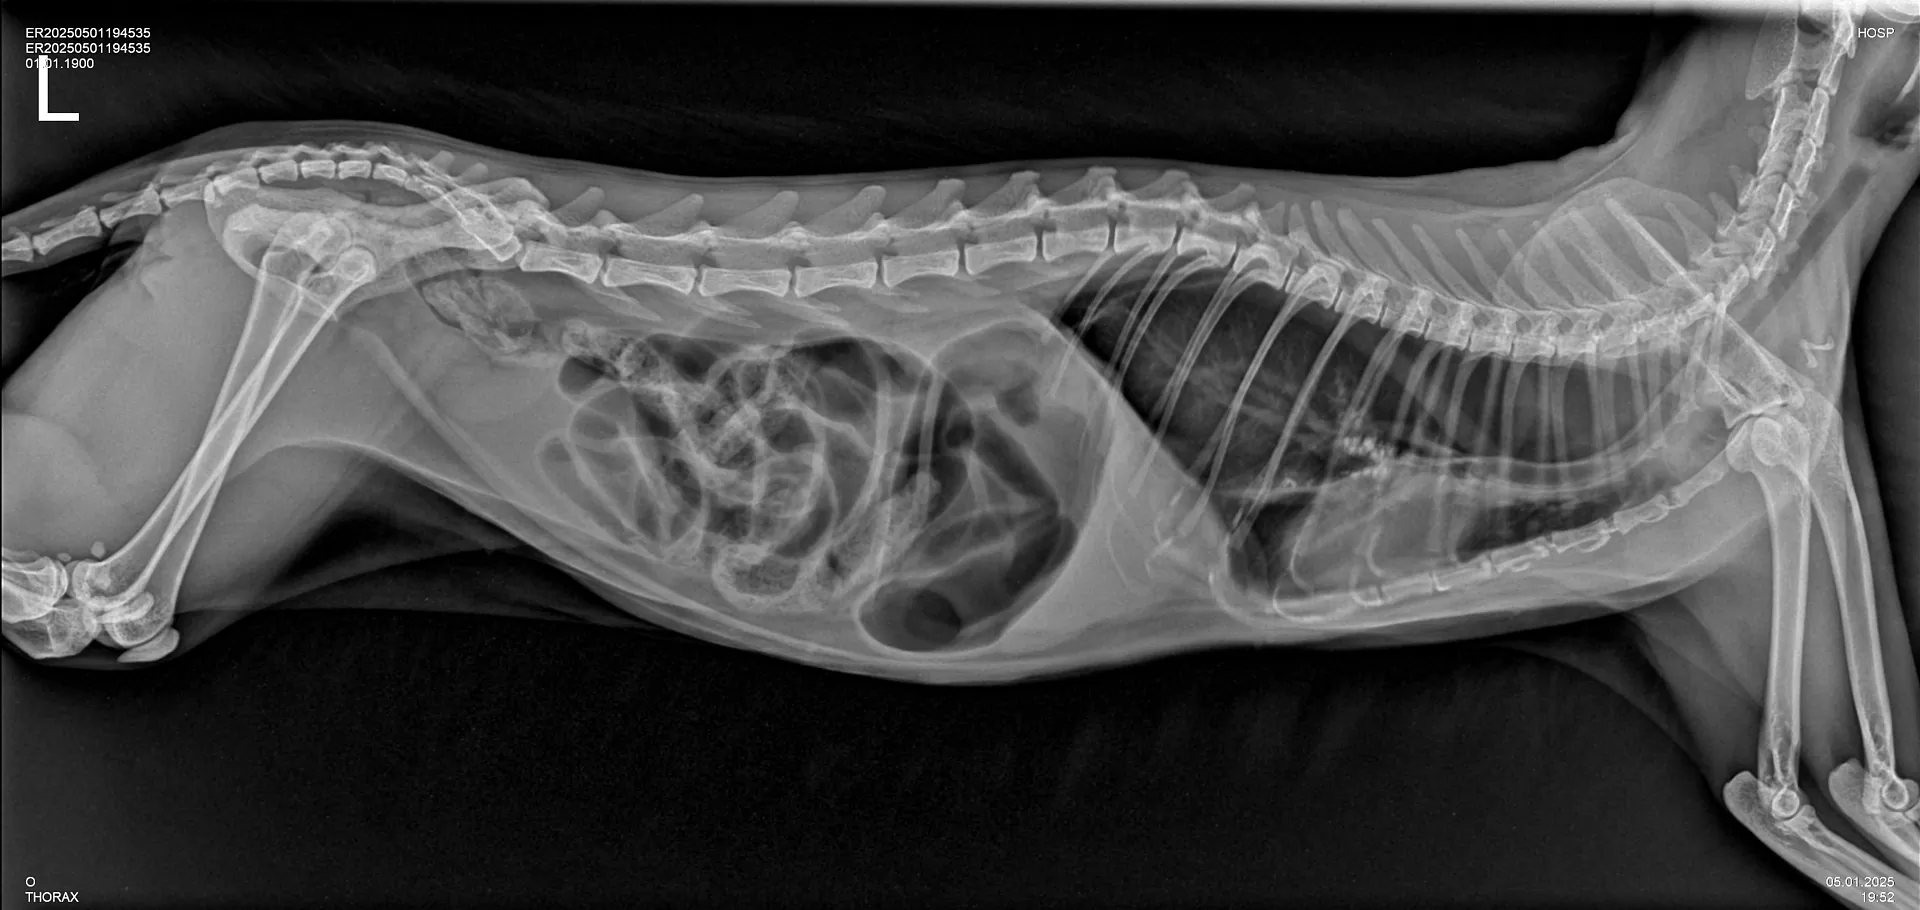

Одним из самых современных и информативных методов диагностики в ветеринарии является рентгенография. В клинике «Умная ветеринария» данный метод исследования проводится для постановки диагнозов при различных заболеваниях животных на цифровом рентген-аппарате высокого класса, позволяя ветеринарным врачам клиники получать ценную информацию о здоровье животных и назначать эффективные варианты лечения.

В ветеринарии рентгенография — это универсальный и незаменимый вид диагностики, один из самых точных, удобных, экономически выгодных для потребителя услуг неинвазивных методов диагностических исследований, используемый для визуализации внутренних структур животных.

Благодаря цифровой рентген-диагностике специалисты «Умной ветеринарии» получают быстрое изображений интересующей области исследования в виде снимка высокого качества на экране монитора, при этом современный цифровой рентген-аппарат, установленный в клинике, адаптирован под нужды ветеринарии, имеет специальное ветеринарное назначение и излучает минимально низкую дозу рентгеновского излучения для пациента, его владельцев, а также для специалиста рентген-кабинета.

Технология рентгенографии основана на использовании рентгеновских лучей, которые проникают через ткани животного. За небольшое количество времени излучение проходит сквозь мягкие ткани, такие как мышцы и внутренние органы, затем оно частично поглощается плотными структурами, такими как кости. Это позволяет получить высокоточное изображение скелета и органов тела животного.

- Для определения патологий органов грудной клетки: легких, сердца, наличия инородных тел в пищеводе. Рентген-диагностика применяется при таких симптомах у животного, как: проблемы с дыханием, обусловленные наличием воспалительных процессов, новообразований, скоплением жидкости в легких (плевральный выпот); сердечная недостаточность, изменение размеров сердца, например его увеличение или кардиомегалия, пневмоторакс (скопление воздуха в грудной клетке), гидроторакс (скопление жидкости в грудной клетке).

- При патологиях органов брюшной полости: кишечной непроходимости, вызываемой обструкцией кишечника проглоченными животным инородными телами или при развитии новообразований/опухолей кишечника. Если животное проглотило несъедобный предмет (игрушку, кость и др), который не вышел естественным путем и вызвал обструкцию, застрял в пищеварительном тракте, рентген-диагностика будет показана в качестве методов исследования первого выбора в комплексе с УЗ-диагностикой, и даст ветеринарному врачу информацию о местоположении инородного тела, его размере и структуре, а также поможет определиться с тактикой лечения. В целях исключения инородного предмета/тел в желудочно-кишечном тракте животного применяется рентгенография с контрастным веществом, которая требует больших временных затрат и подготовки в виде применения у животного контрастного вещества, но чрезвычайно эффективна и распространена в ветеринарной практике.

- Рентген-диагностика у животных на определение беременности и количества плодов. В отличие от людей, у животных рентген-диагностика активно применяется в случаях, когда необходимо не только подтвердить или исключить факт наступления беременности у животного, но и с большей точностью, чем при УЗ-диагностики, определить количество плодов при беременности. Именно цифровая рентгенография полностью безопасна для самой будущей матери и ее потомства в этом случае.

Во время процесса рентгенографии рентгеновские лучи фиксируются на цифровой панели, создавая темный силуэт скелета животного на белом фоне. Мягкие ткани, внутренние органы, отображаются в виде различных оттенков серого в зависимости от их плотности.